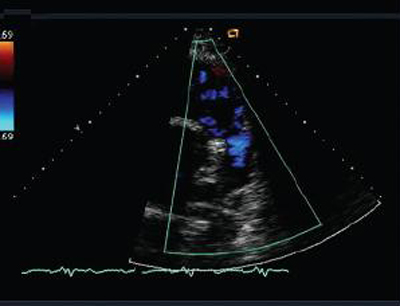

Doppler echocardiogram in a patient with pulmonary regurgitation following repair of tetralogy of Fallot, revealing a non-obstructed right ventricular outflow tract. The patient has a non-restrictive right ventricle

From: Chaturvedi RR, Redington AN. Heart. 2007 Jul;93(7):880-9; used with permission